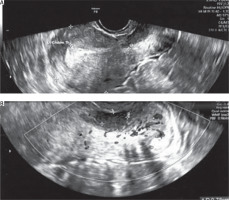

She suffered from abnormal vaginal bleeding for eight months, occurring 7–10 days before her menstruation and lasting 2–3 days, with no other complaints such as pelvic pain or vaginal discharge. During a gynaecological examination with a speculum, a lesion protruding from the cervical canal was observed. A transvaginal ultrasound showed a cervical tumour measuring 25 × 21 × 32 mm. Two months earlier, a Pap smear taken during a routine check-up did not indicate the presence of cancer cells. A test for high-risk oncogenic HPV was negative (Figure 1).

Figure 1

Picture from the TV ultrasound. A) Uterine body with a visible lesion in the cervix. B) Lesion visible at closer zoom at greater magnification